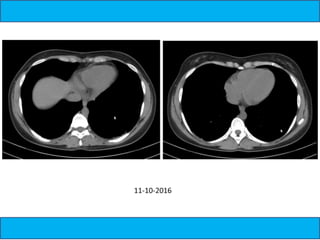

A medical document discusses hypoxia following a road traffic accident. It describes four types of pulmonary contusion caused by direct chest compression, shearing against vertebral bodies, fractured ribs directly injuring the lung, or tearing of lung parenchyma due to prior adhesions. The document also mentions management of pulmonary contusion.